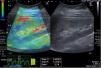

A case of acute interstitial nephritis post chemotherapy with mild interstitial fibrosis (10%). The greyscale ultrasonography image showing mild increased parenchymal echogenicity with preserved cortico-medullary differentiation, the left one showing color-coded US – elastography image showing mainly green-red scale and the sinusoidal wave of compression and decompression seen in inferior aspect of image. The circles indicate the region of interests (ROIs). The upper ROI is on the parenchyma and the lower ROI is on renal fat sinus. The radial line on the sinusoidal wave indicates the end measurement (SI=0.74).